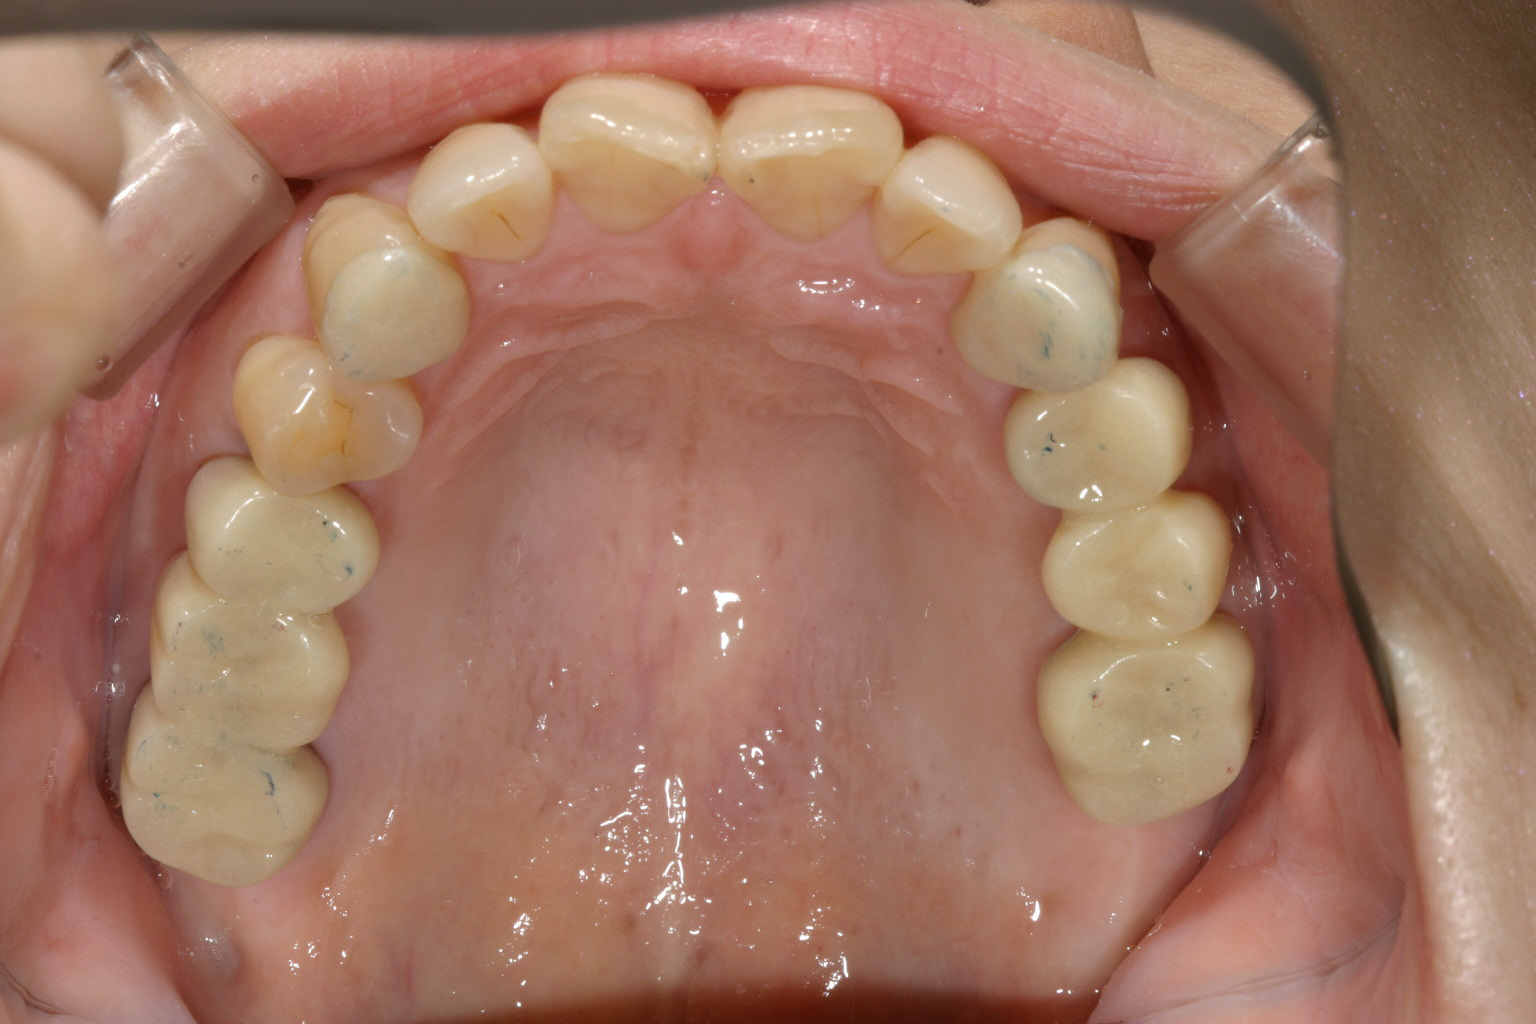

奥歯の両サイドのブリッジを適切な高さを与えてやり直しました。

下顎も奥歯の両サイドを適切な高さを与えてブリッジにしました。